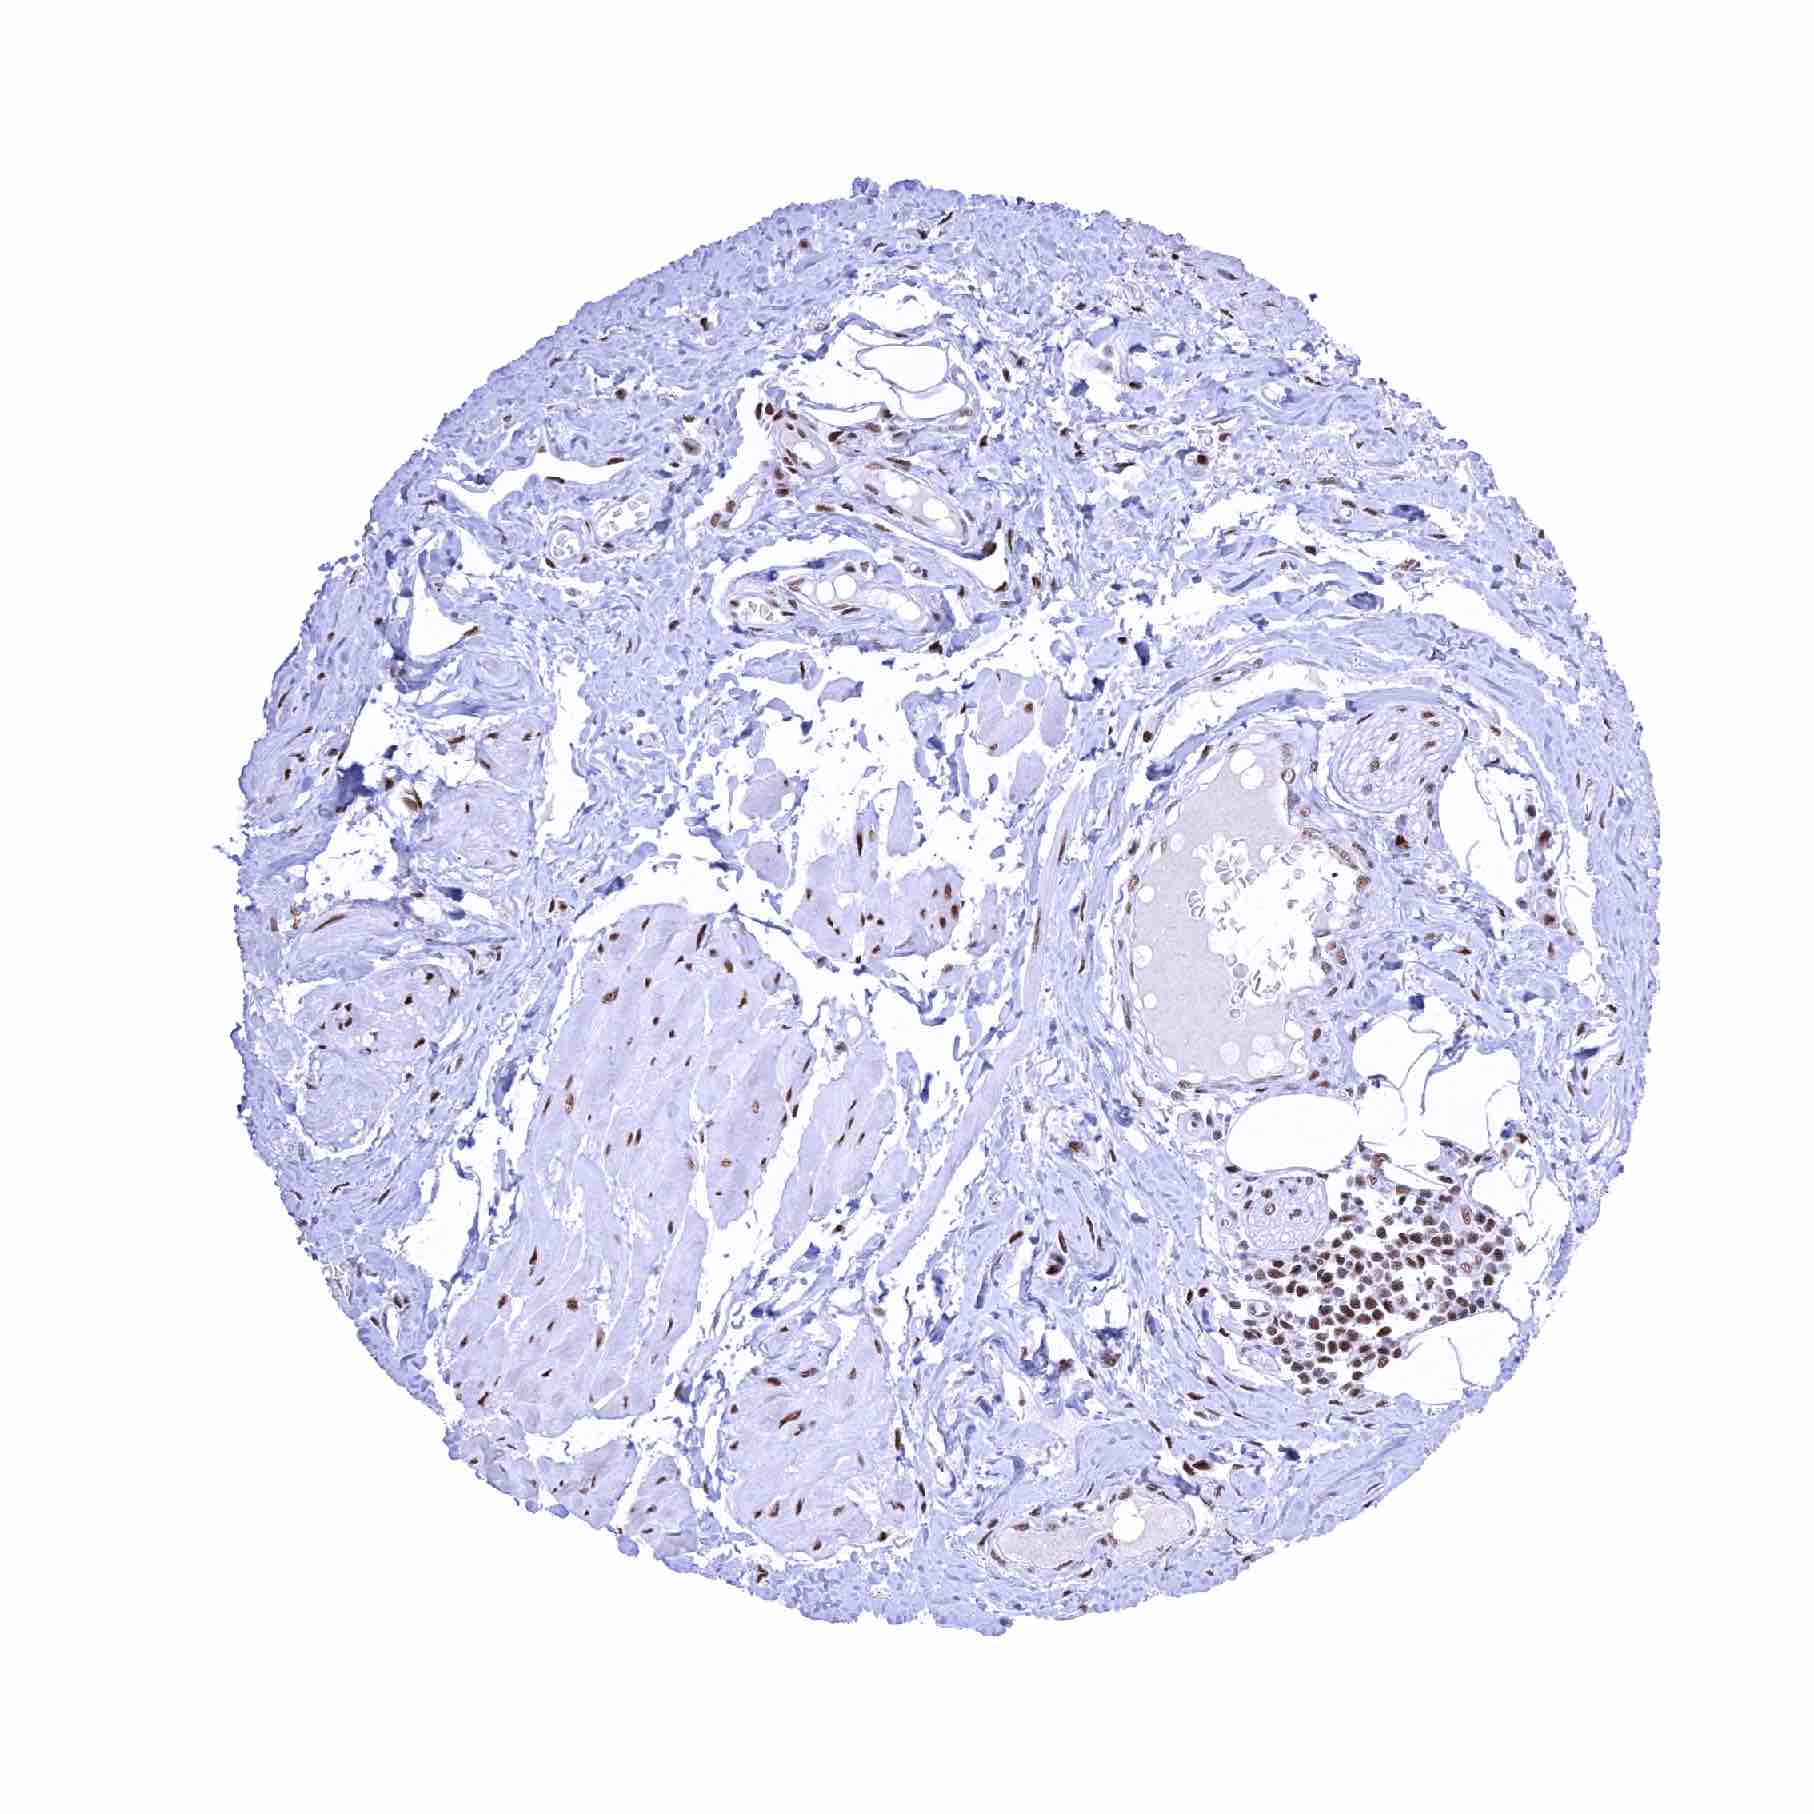

Normal Tissue Gallery- GTX640556

53BP1 antibody [HMV324] HistoMAXTM

Adrenal gland